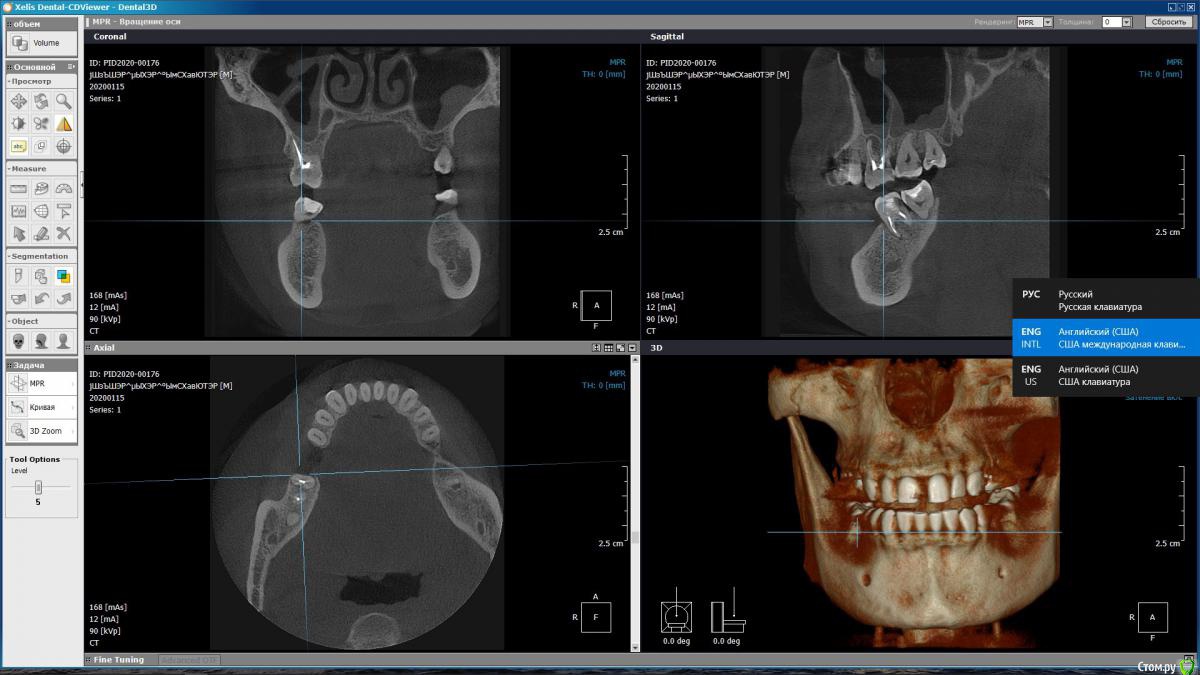

m-e-a Опубликовано 19 января, 2020 Автор Поделиться Опубликовано 19 января, 2020 (изменено) Сделала срезы как смогла, не умею я смотреть КТ Изменено 19 января, 2020 пользователем m-e-a Ссылка на комментарий

red_butler Опубликовано 19 января, 2020 Поделиться Опубликовано 19 января, 2020 На представленных срезах, показаний к удалению не увидел. Нужно смотреть очно и «крутить» Кт Ссылка на комментарий